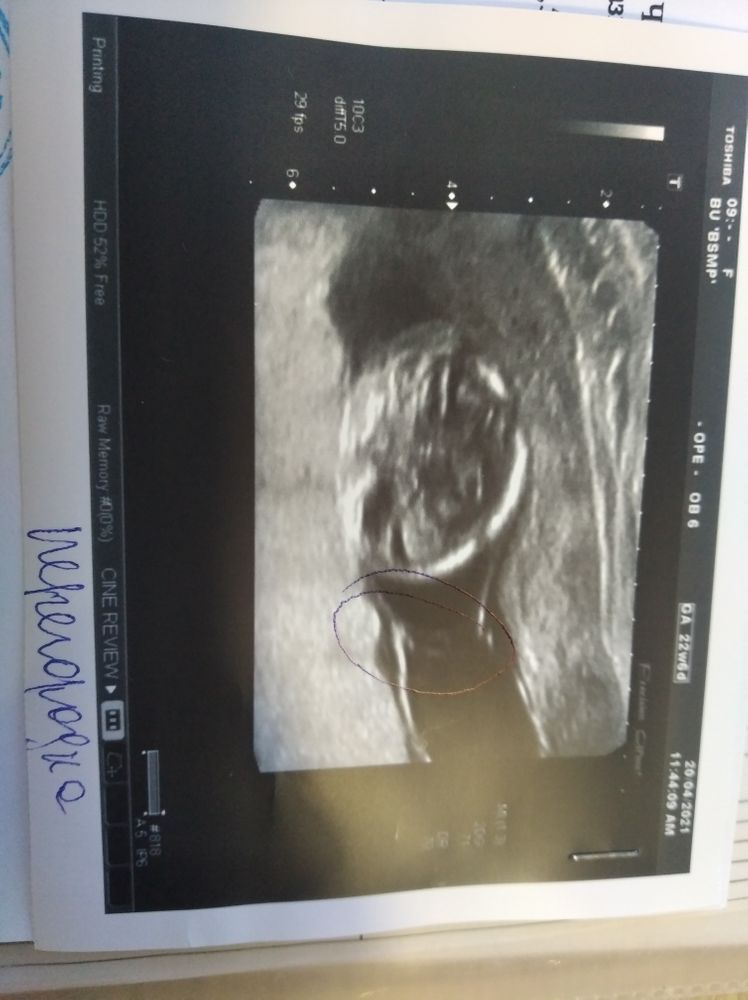

Но увы. У нас никогда не бывает просто так, всегда загадки) Никаких изменений не нашли, очевидных выводов не сделали. В выписке написали :" больше данных за монохориальную диамниатическую двойню" и приложили вот такое фото...😝😝😝

Не перевернулось почему то..

Я конечно не спец, нона фото ощущение одного плодного пузыря.

Ирина, в 7 недель мне тоже Ди/Ди написали, но сказали перегородки не видно, так и не нашли, но сейчас моно/Ди. Хотя вот что за место обведено на фотографии.. загадка прямо. Ощущение что мальчики это. Вообще ни разу чуйка не подводила, но в нынешнем случае даже не знаю

Сомневаются моно-моно или моно-ди? Вроде бывают случаи неполной перегородки